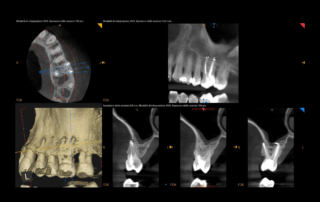

Dente compromesso o possibilità?

C’è chi vede un dente compromesso e chi invece una possibilità.✨

In questo caso clinico, un trauma aveva lasciato un dente discromico e necrotico, con canale radicolare calcificato.

Un trattamento complesso, affrontato sotto microscopio, ha […]